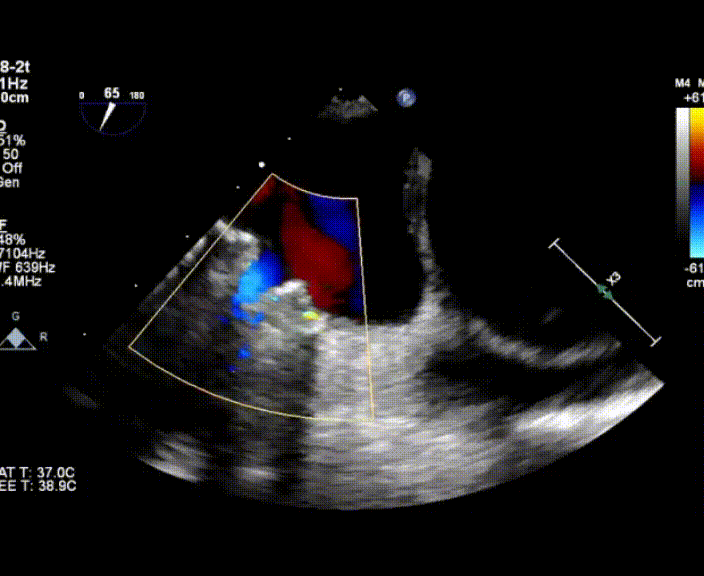

術(shù)中首先在局麻下穿刺股動脈、股靜脈,完成心導(dǎo)管檢查評估后轉(zhuǎn)為全麻,在食道超聲引導(dǎo)下穿刺房間隔,穿刺成功后將加硬導(dǎo)絲送入左上肺靜脈建立軌道,根據(jù)患者病情行球囊預(yù)擴(kuò)張后植入6mm孔徑房間隔造孔支架,經(jīng)透視及食道超聲評估支架左右盤展開良好,夾持于房間隔兩側(cè),固定穩(wěn)定、位置良好,食道彩超顯示房水平右向左為主分流,分流孔直徑符合預(yù)期大小,心導(dǎo)管檢查評估達(dá)到預(yù)期效果,釋放造孔支架。術(shù)后12h患者下床活動,恢復(fù)順利,擬于近日完善術(shù)后評估后出院。